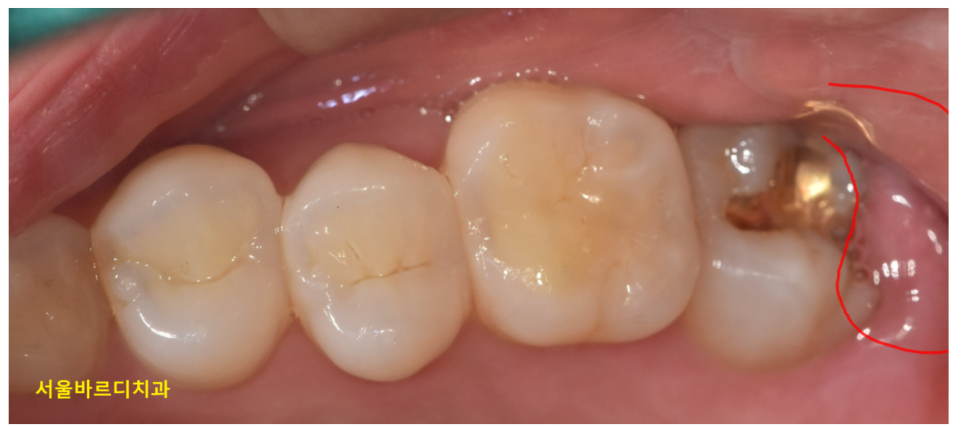

그 외에 치아가 깨졌다거나..

보철물에 염증이 생겼다거나

원인은 정말 다양하답니다!

250424 사랑니로인한 잇몸 부음일 수도 있죠.

22.12.16~23.11.18 치아에 때가 많이 껴도 잇몸이 부을 수 있습니다.